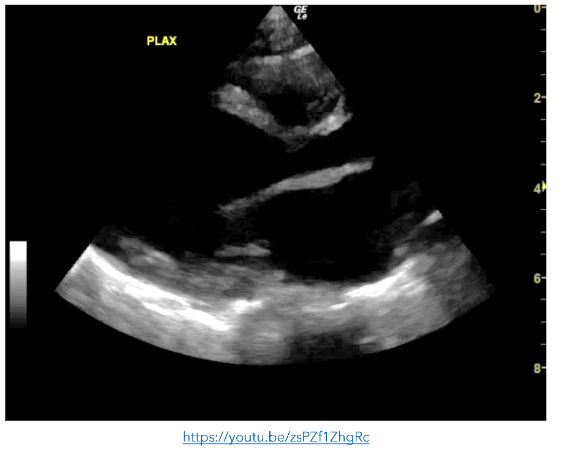

Figure 2: PLAX view showing a hyperdynamic left ventricle. There is a pericardial effusion present.

A previously well 9 month-old was brought to the ED by her mother with a recent history of bronchiolitis in the preceding 10 days. Although her initial upper respiratory symptoms had resolved, she now had reduced oral intake and urinary output. On assessment, the infant was tachypnoeic, tachycardic and had bilateral patchy infiltrates on CXR. As the baby was unwell with an undifferentiated shock, POCE was performed. It demonstrated very poor contractility of the left ventricle which contributed to a working diagnosis of myocarditis.

Figure 4: PLAX view showing and enlarged left ventricle with very poor contractility